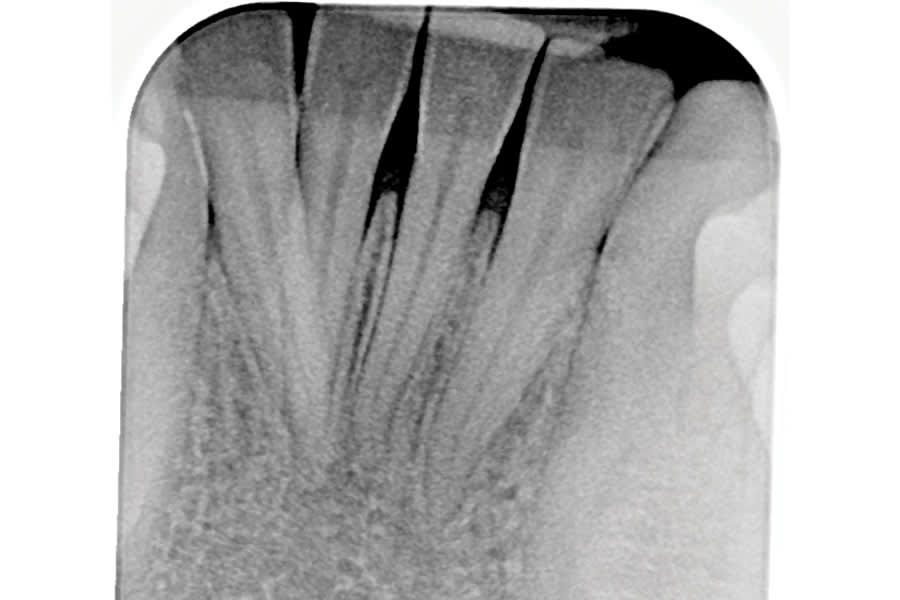

A second option is to use corrective orthodontic therapy in the form of fixed appliance application to torque the root back into the correct position (Figure 5 through Figure 7). This requires full-sized archwire insertion into a precision edgewise bracket (Figure 7). This can be a time-consuming undertaking, as the step-up through various archwires until fully engaging a full-sized wire will take a few months. Nevertheless, significant corrective changes often can be observed, as the tooth's investing structures often spontaneously remodel, at least partially, in response to the corrected tooth position (Figure 5 and Figure 7, Figure 11 and Figure 13).

A third option for correcting tooth position is via orthodontic aligner therapy (Figure 8 through Figure 13). With this modality, precise 3-dimensional control must be designed and incorporated into the aligner prescription. This option presents a more expedient alternative than the use of conventional fixed appliances, because the aforementioned stepwise progression of increasing the size of archwires is unnecessary, and corrective force can be applied from the onset (Figure 12). Significant overcorrection of the intended movement is recommended in the prescription. In this way, if the aligners do not fully express the movement, continued usage of them may accomplish it. Should the result be attained prior to the conclusion of all aligners, cessation (and more appropriate retention) is indicated.